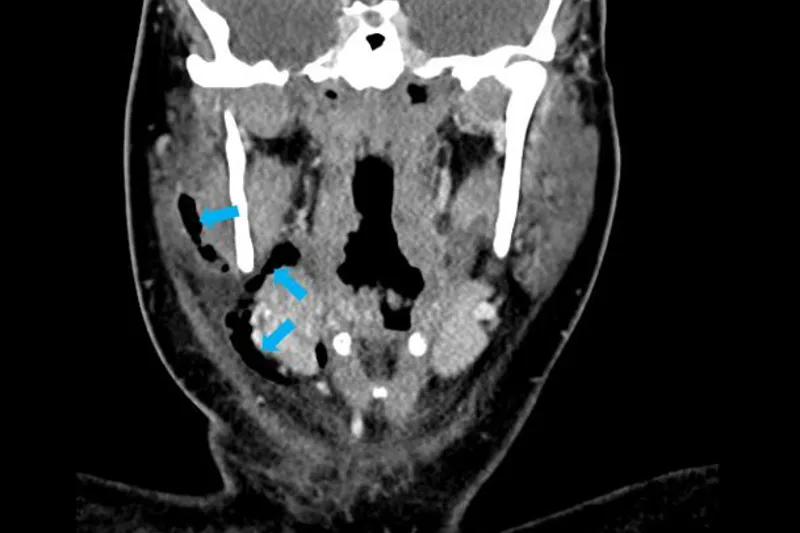

29-årig kvinde blev indlagt med emfysem efter operativ fjernelse af underkæbens tredjemolar. Behandlingen var antibiotika, observation samt incision og drænage af den ledsagende absces. Under fjernelse af tanden opstod der en større laceration sublingvalt i mundslimhinden, som formodes at have tilladt luftadgang ved nys.